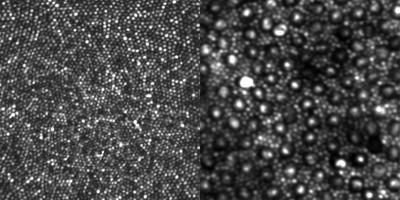

Adaptive optics was first developed by astronomers so that telescopes could see more clearly through the Earth’s atmosphere. The technologies that Williams and his group developed apply these techniques to the eye and make it possible to image individual retinal cells—including down to individual cone photoreceptors in the living human retina—by looking through the pupil. The techniques Williams’ group developed can not only modify the light leaving the eye to obtain better pictures of the retina, they can also modify the light going into the eye to produce better vision. This can improve vision in patients with contact lenses, intraocular lenses, and laser refractive surgery. For example, the methods Williams’ group developed are used in many of the LASIK procedures conducted worldwide today.